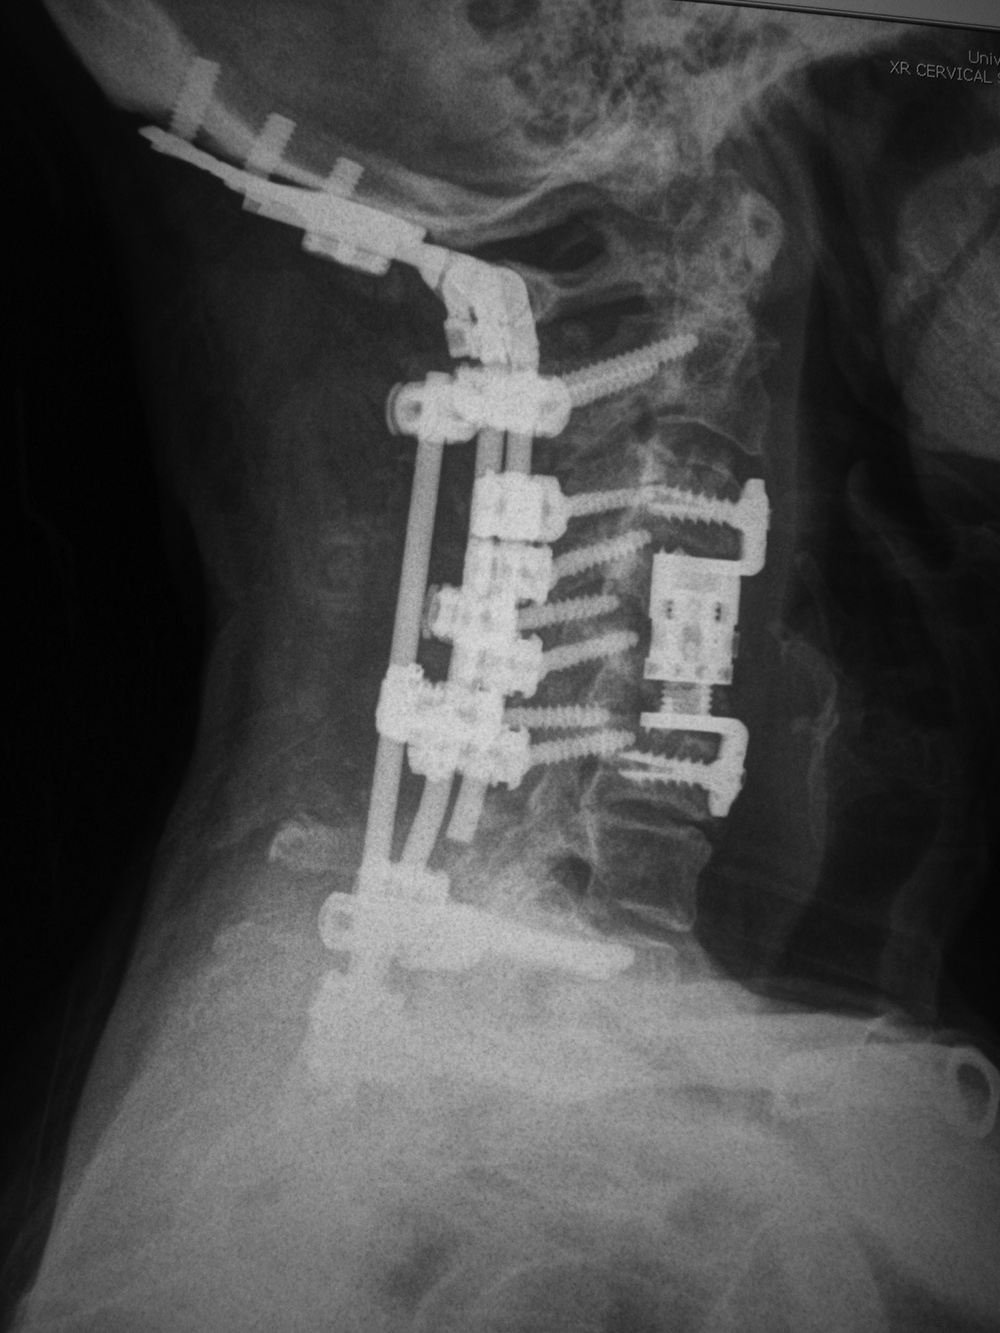

Cervical spine anterior and posterior fusion |

Young woman with traumatic locked facets at C6-7 and C7 body fracture. A posterior cervical fusion with lateral mass screws (cervical spine) and pedicle screws (thoracic spine) and rods extends from C4 to T2. There is an anterior cervical fusion plate and screws at C6-7 with a intervertebral disk cage at C6-7 and a crosslink at C6. |